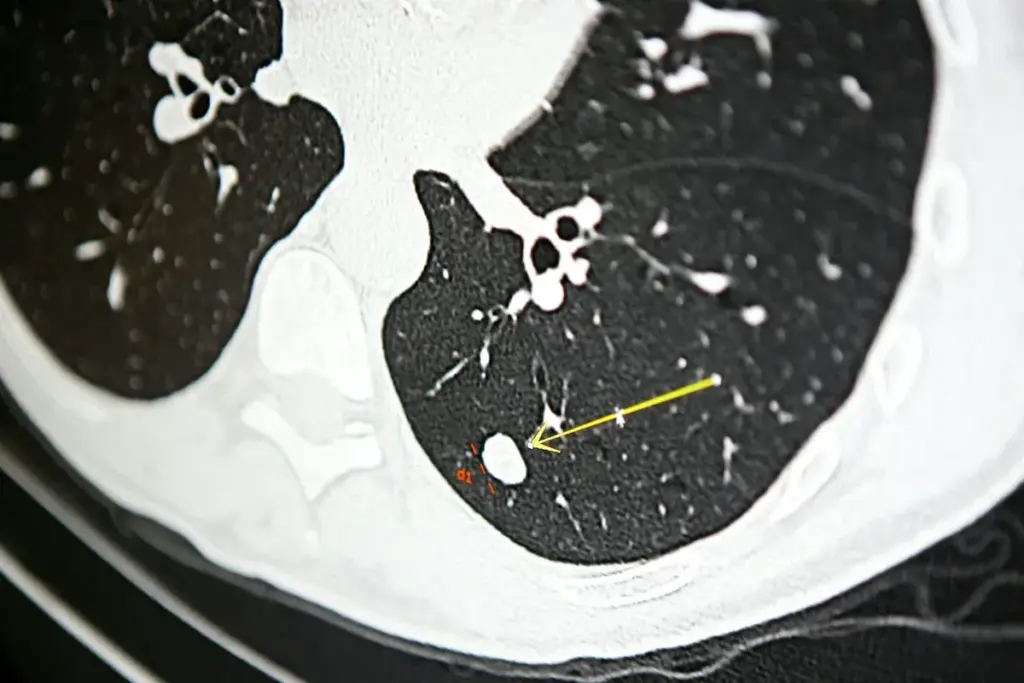

Limitations of PET Scans for Lung Nodule Evaluation

PET scans are useful for checking lung nodules, but they have some limits. Knowing these limits helps doctors make better choices and give accurate results.

False Positive Results

PET scans can sometimes show cancer where there isn’t any. This is called a false positive result. It happens when something like an infection or inflammation makes a nodule look like cancer.

Infectious diseases can make this problem worse. In places where infections are common, PET scans might show false positives more often. This is because infections also make cells use more sugar, just like cancer does.

Reduced Specificity in Regions with Prevalent Infectious Diseases

In areas with lots of infections, PET scans aren’t as reliable. Studies show that in these places, the scans might only be right 40-66% of the time. This means more people might get extra tests or treatments that aren’t needed.

Size Limitations for Small Nodules

PET scans also struggle with small nodules. They can’t always tell if a nodule is small enough to be cancer. This is because the scans can’t see very small details well. So, small nodules might be misdiagnosed as cancer or not cancer.

Doctors need to know these limits to understand PET scan results. This helps them make the best choices for their patients.